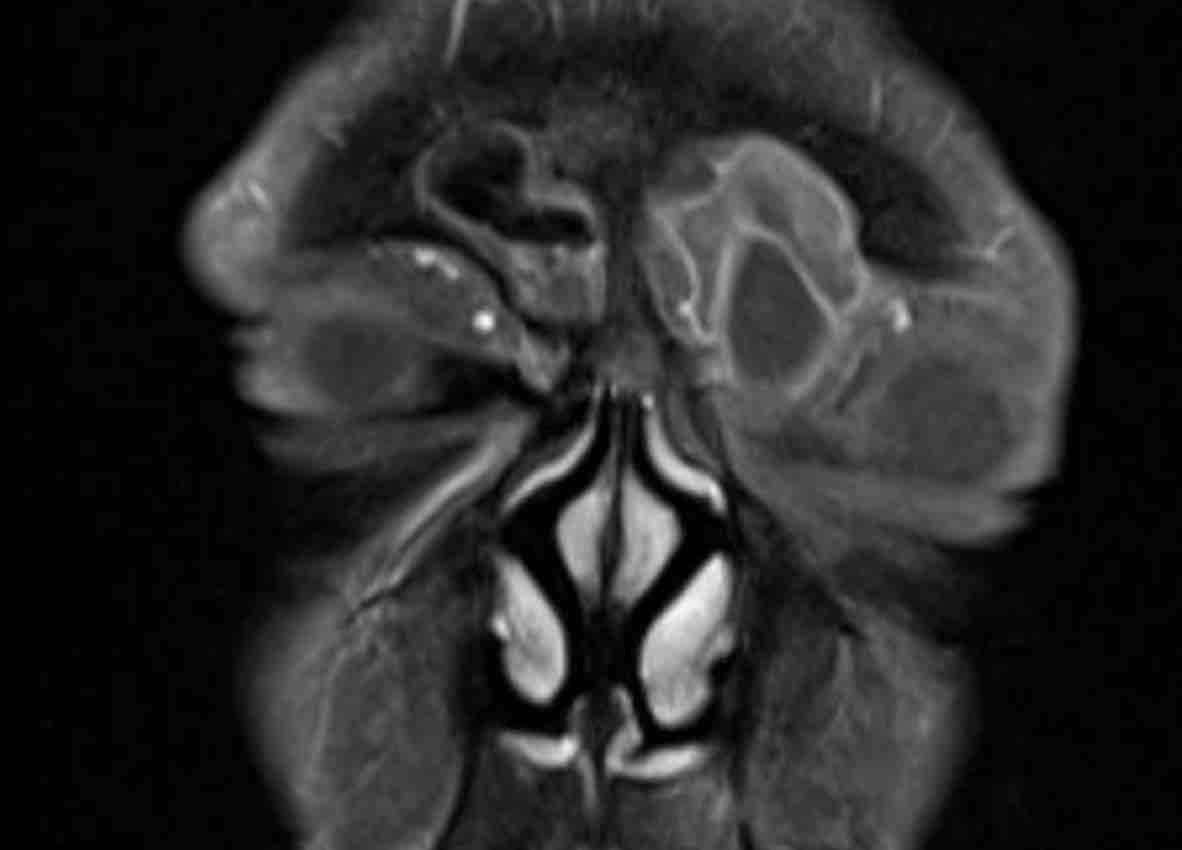

MRI được thực hiện để xác nhận chẩn đoán nhiều khả năng nhất là nang nhầy…

MRI cho thấy tổn thương giãn rộng chỉ có ngấm thuốc tương phản từ ở vùng viền ngoại vi.

Không có ngấm thuốc bên trong tổn thương.

Điều này xác nhận chẩn đoán nang nhầy.

Nang nhầy là tổn thương dạng nang chứa đầy chất nhầy.

Nang hình thành khi lỗ thông của (một phần) xoang cạnh mũi bị tắc nghẽn.

Cuộn qua các hình ảnh MRI.